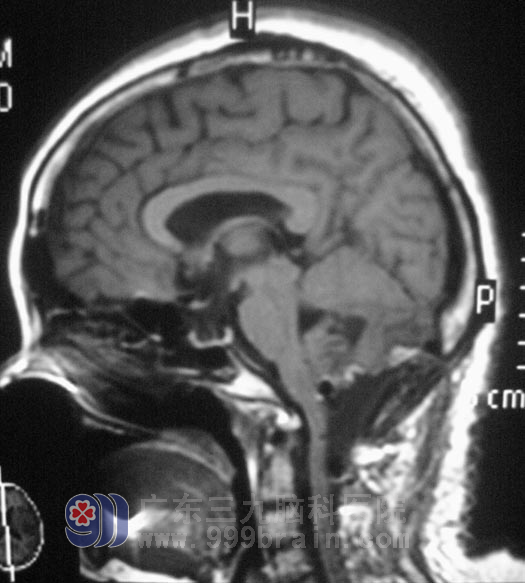

年过50的卢女士,5个月前开始出现左侧肢体麻木、乏力,偶有头痛、头晕,无恶心、呕吐,在当地医院治疗后,症状没有明显好转,并逐渐出现行走困难,视物重影,左侧眼球外展受限,构音障碍,饮水呛咳,吞咽有哽住感,左侧耸肩稍差,左侧胸锁乳突肌有萎缩。7月29日,医院头颅MR检查示“枕骨大孔区占位,大小约3cm×3cm,呈囊实性”,广东三九脑科医院综合神经外科鲁明主任结合影像和病史表现,初步考虑为“血管母细胞瘤”。

8月23日,鲁明主任主刀,在全麻下行“后正中入路延髓肿瘤切除术”,术中可见囊壁暗褐色病变组织,小脑组织有所塌陷,肿瘤实性部分位于延髓至第二颈椎髓外硬膜下,呈暗褐色,血供丰富,在显微镜下小心分离,完整切除,直径约3cm,术中后组颅神经、脑干及重要血管均予解剖保留完整,术中出血约400ml,手术历时9小时。术后2小时患者完全清醒,能遵嘱活动,四肢活动正常。术后第三天,患者神志清醒,自诉头痛、头晕症状好转,构音清晰,已恢复正常进食。术后经病理证实为:(枕骨大孔区)毛细血管性血管母细胞瘤。